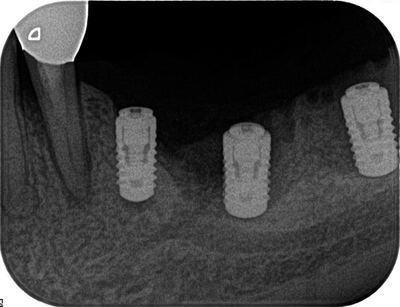

オペ後のレントゲン写真です。